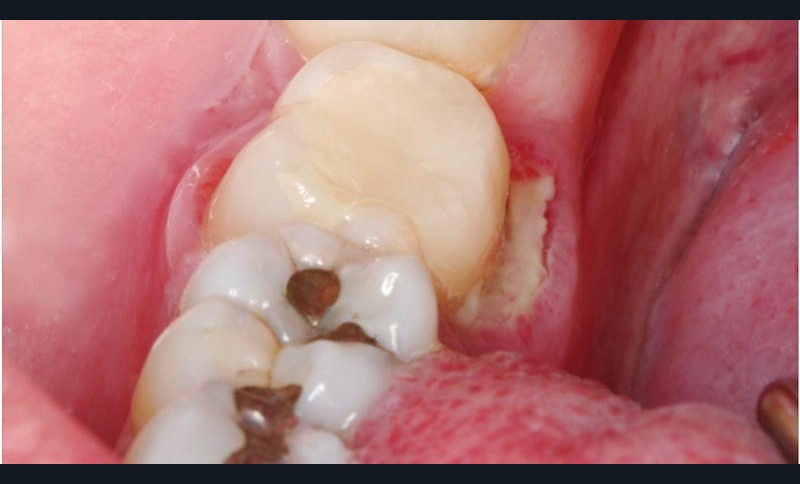

Sur la 47, on observait une volumineuse obturation provisoire reconstituant la face linguale et une exposition de l’os alvéolaire, au contact de la 47, sur toute la longueur de la face linguale et sur une largeur de 6 mm.

Le séquestre osseuxn’était pas visible sur la radiographie rétro-alvéolaire. L’examen histopathologique du séquestre (10 x 6 x 1,5 mm) a confirmé qu’il s’agissait d’un séquestre osseux avec quelques lacunes d’ostéoclasie en périphérie et parfois un ostéoclaste. On notait également par endroits la présence de très rares corps étrangers pulvérulents,brunâtres, très faiblement biréfringents en lumière polarisée,correspondant probablement à un produit dentaire.